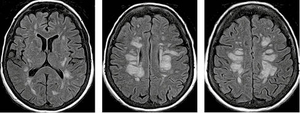

На рисунку 4 наведено МРТ-зображення головного мозку пацієнта з гострим геморагічним лейкоенцефалітом (хворобою Херста) у режимі Т2*/T2 GRE, де візуалізуються двобічні гіперінтенсивні вогнища, два з яких містять геморагічний компонент, та в режимі Т2. А на рисунку 5 — МРТ-зображення головного мозку пацієнта з ГРЕМ у режимі Т2 — продемонстровано важливу ознаку ГРЕМ (на відміну від РС): відносну інтактність мозолистого тіла, стовбура мозку, середніх мозочкових ніжок та мозочка, які в разі РС, як правило, уражаються першочергово. Вказана ознака не завжди є показовою, але має високу інформативність для диференційної діагностики.

/images/nn257-1622023r4_.jpg)

/images/nn257-1622023r5_.jpg)